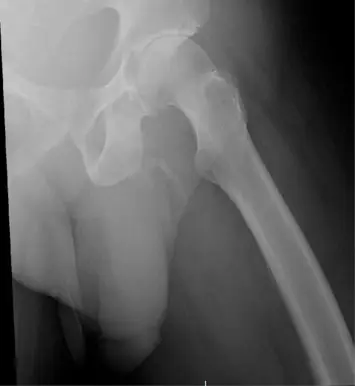

As per the Urology Case Report, the man's 'physical exam was negative except for a penile pain', sparking him to undergo an x-ray 'to rule out any fracture showed a severe, asymmetric degenerative changes of the right hip'.

But doctors discovered something unexpected when the results of the scan came back, and it turned out it had nothing to do with the man's hip.

The patient went on to be diagnosed with penile ossification - an extremely rare condition with fewer than 40 cases reported.

Penile ossification occurs when calcium salts build up in the soft tissue of the penis, forming extraskeletal bone.